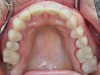

Fig 3. Occlusal view with posts inserted.

Figure 3

Diagnostic models were taken and the existing plane of occlusion was captured with the Kois Dento-Facial Analyzer (Panadent; panadent.com) and a CR bite and sent to VIVIDX Laboratory. The treatment plan included elective root canal treatment and cast post and cores for teeth Nos. 7 to 10. Onlays, seven or eight crowns, and full crowns were planned to restore the maxillary dentition. An Essix (Colgate; colgate.com) retainer was made from the original design to establish the new vertical dimension and relined with composite to obtain anterior esthetics. This was used as a temporary restoration after minimal preparation and impression of the maxillary teeth.

The cast post and cores were fabricated along with the transitional restorations for all maxillary teeth. Cast post and cores were cemented and all onlays and crowns were bonded in. Occlusion was checked with only minor adjustments necessary. Anterior guidance was reestablished.

Cast post and cores were fabricated on the stone casts with Noritake opaque applied to the outer surfaces to block the metal. The maxillary master cast was re-scanned with cast posts seated on a model and merged with the original design.